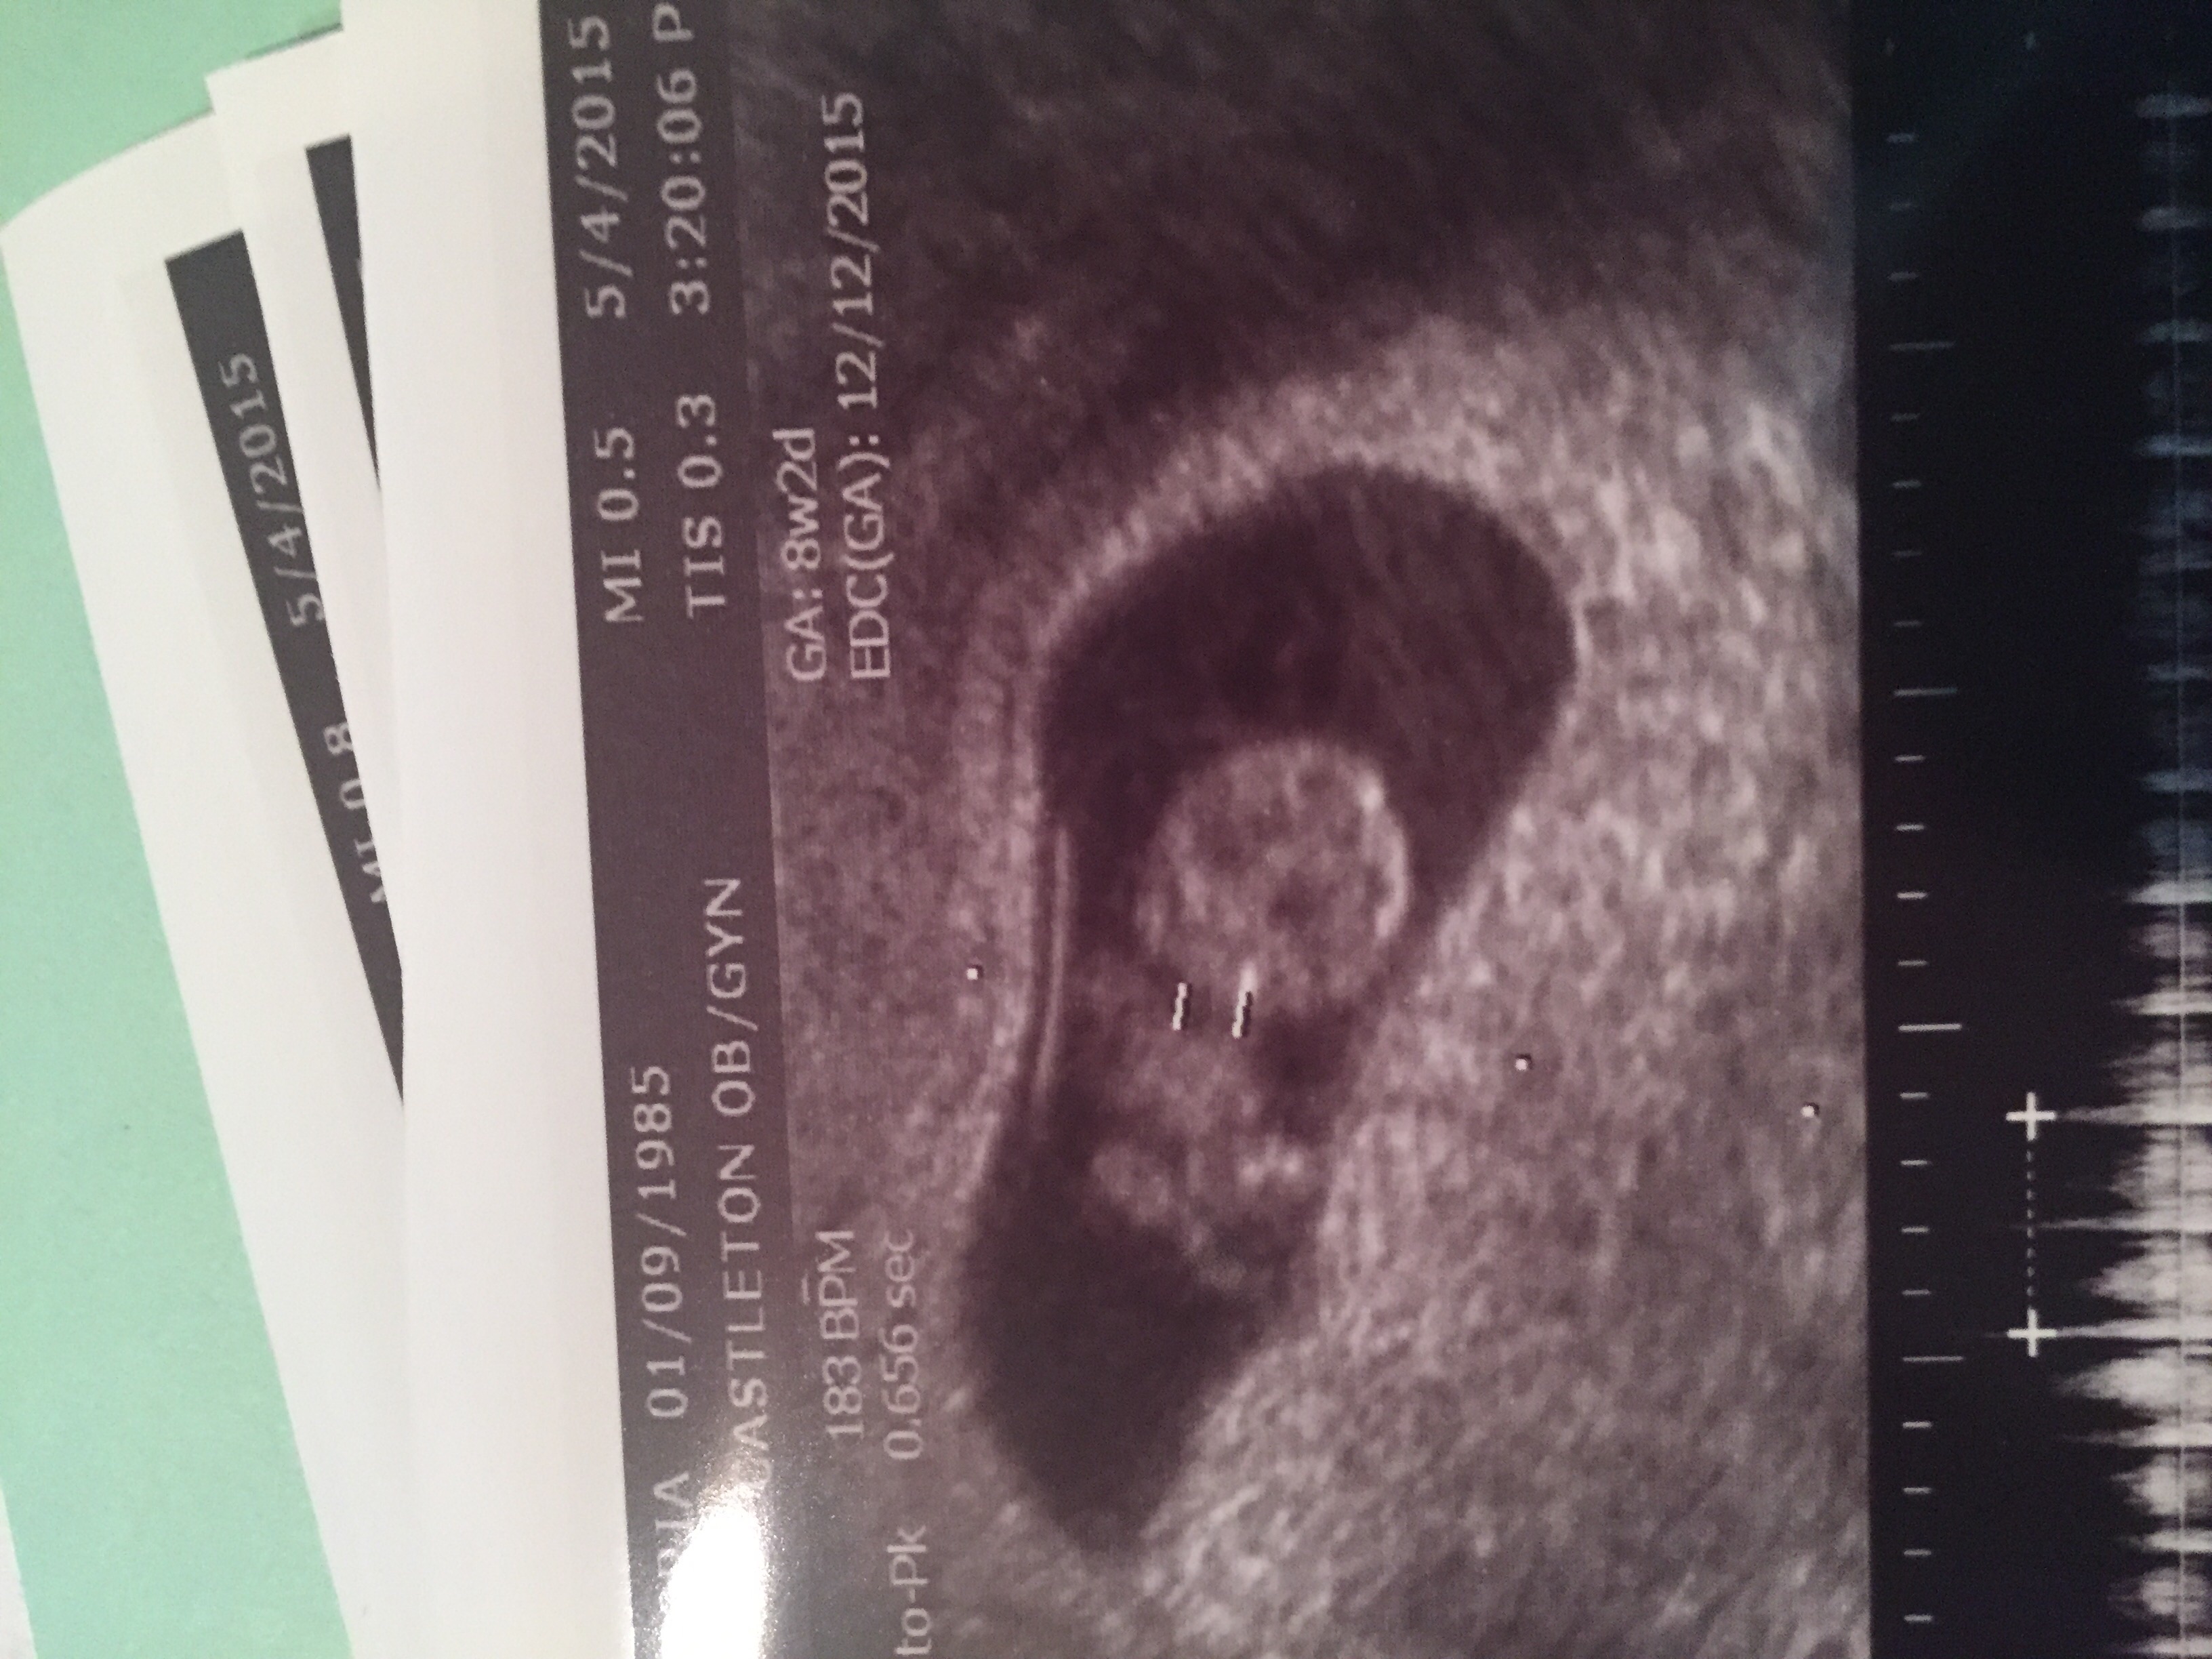

I don't have my pictures scanned in, but I guess I need too now! Wow I can't believe how baby like it looks at 9 weeks! That is insane. I got to see the heart beat, but my OB said we would listen next time!!! So excited!